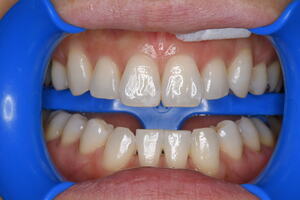

セレックインレーの不適合で虫歯が再発

適合が悪いため、虫歯が再発 虫歯を取り除き治療終了